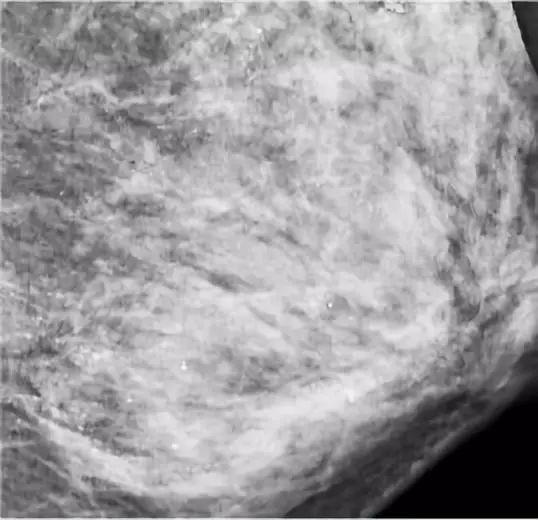

48岁的朱女士亲身体验了一把。在进行乳腺钼靶X线摄影检查时,医生发现朱女士的左侧乳房布满众多细小如沙子一样、呈散在分布的钙化灶,并且无法轻易判断哪些是良性,哪些是恶性。

▲钼靶检查发现,朱女士乳腺里满是星星点点的钙化灶 。

一般来说,乳房内部出现钙化灶,原因很多:可能是炎症或损伤渗出物留下的痕迹、新陈代谢后的钙盐沉积,也有可能是肿瘤造成的组织变化。